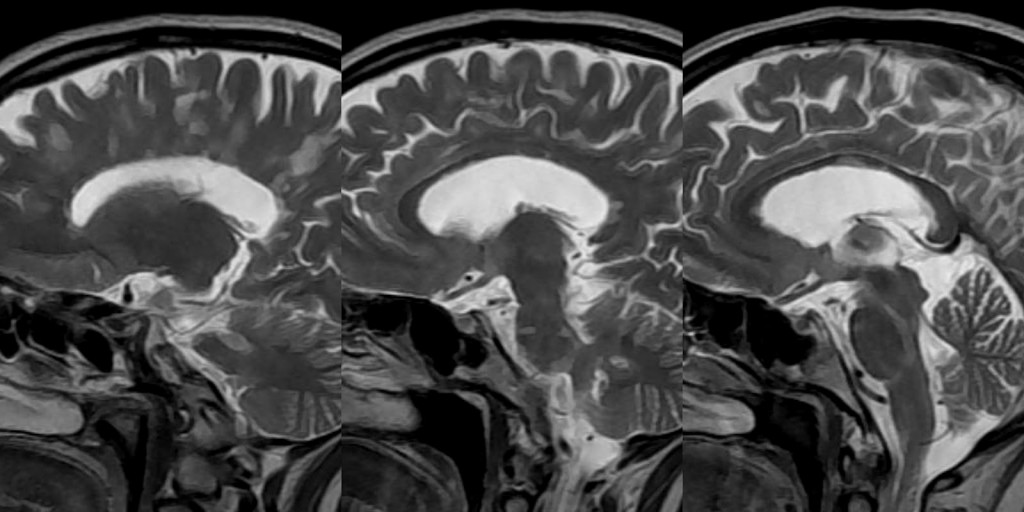

In 1992, these doctors that I mentioned who had focused on Lake Tahoe came out with a study in the Annals of Medicine, and it documented a variety of abnormalities — abnormal MRI brain scans, lowered white blood cell counts and functioning, HHV6 and more.